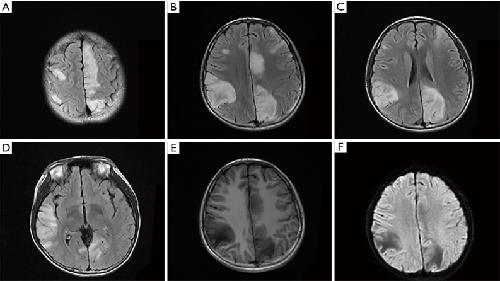

Kv3.1 channelopathy: a novel loss-of-function variant and the mechanistic basis of its clinical phenotypes., Li X, Zheng Y, Li S, Nair U, Sun C, Zhao C, Lu J, Zhang VW, Maljevic S, Petrou S, Lin J., Ann Transl Med. September 1, 2021; 9 (18): 1397.